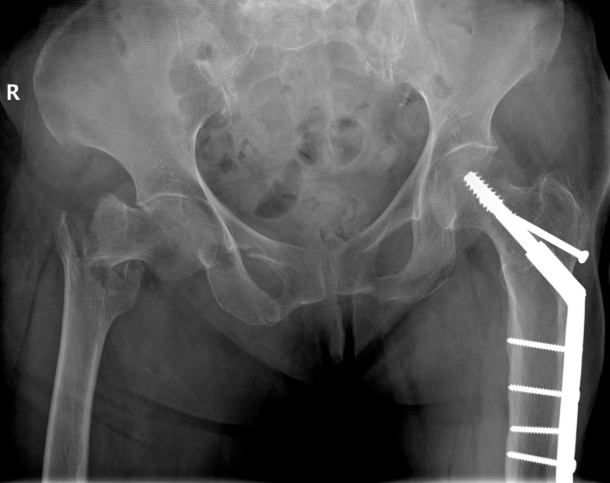

新突破∣“黄金手术期”破解骨科高龄患者手术难题